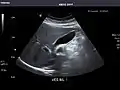

Left kidney

Kidneys: Right and left kidneys measure 11.5 cm and 12 cm in length respectively. No hydronephrosis. Small left lower pole kidney cyst.